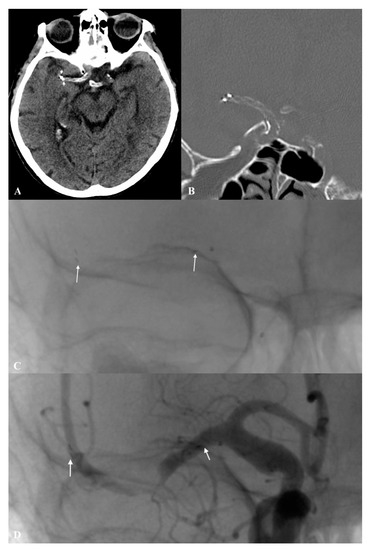

3.1. Case Study

3.1.1. Patient No. 1

3.1.2. Patient No. 2